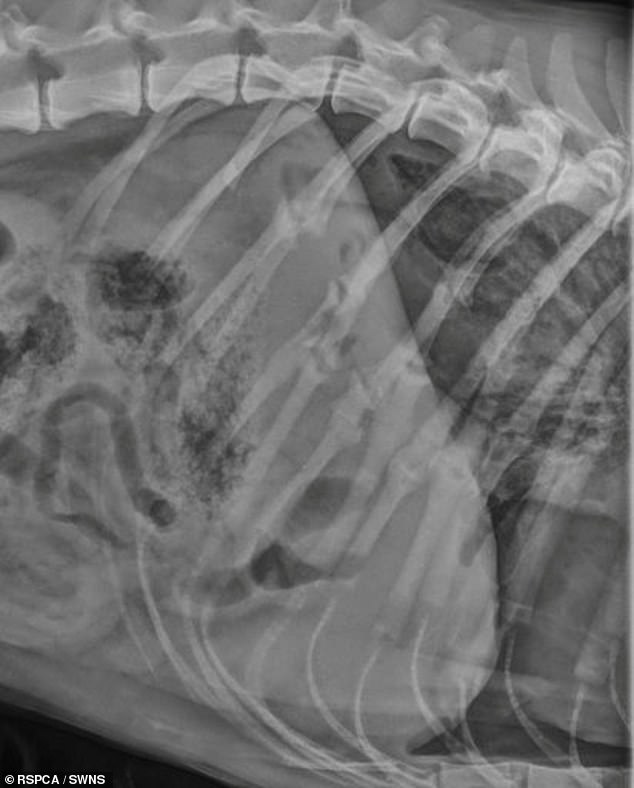

- Dog's broken body had more than 25 rib fractures, ruptured windpipe and more

30-year-old Andrew MacKay, of Pulton-le-Fylde, Lancs, left the broken body of his grey crossbreed dog, Bonzo with so many fractures that experts could not officially determine how many injuries he sustained.

Further investigations later revealed Bonzo had suffered so many fractures that experts were unable to determine exactly how many he had obtained, the court heard.

Andrew MacKay, 30, (right) of Pulton-le-Fylde, Lancs, left pet dog Bonzo with rib fractures, an eye socket fracture, a cheek fracture, ruptured windpipe and injuries to his face

Further investigations later revealed Bonzo had suffered so many fractures that vets were unable to determine exactly how many he had obtained, the court heard. Bonzo's X-ray (above)